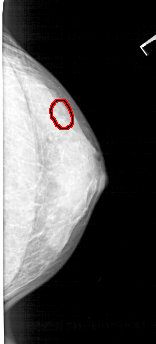

FILE: A_1352_1.RIGHT_MLO.OVERLAY

TOTAL_ABNORMALITIES 1

ABNORMALITY 1

LESION_TYPE CALCIFICATION TYPE PLEOMORPHIC DISTRIBUTION CLUSTERED

ASSESSMENT 4

SUBTLETY 2

PATHOLOGY BENIGN

TOTAL_OUTLINES 1

BOUNDARY